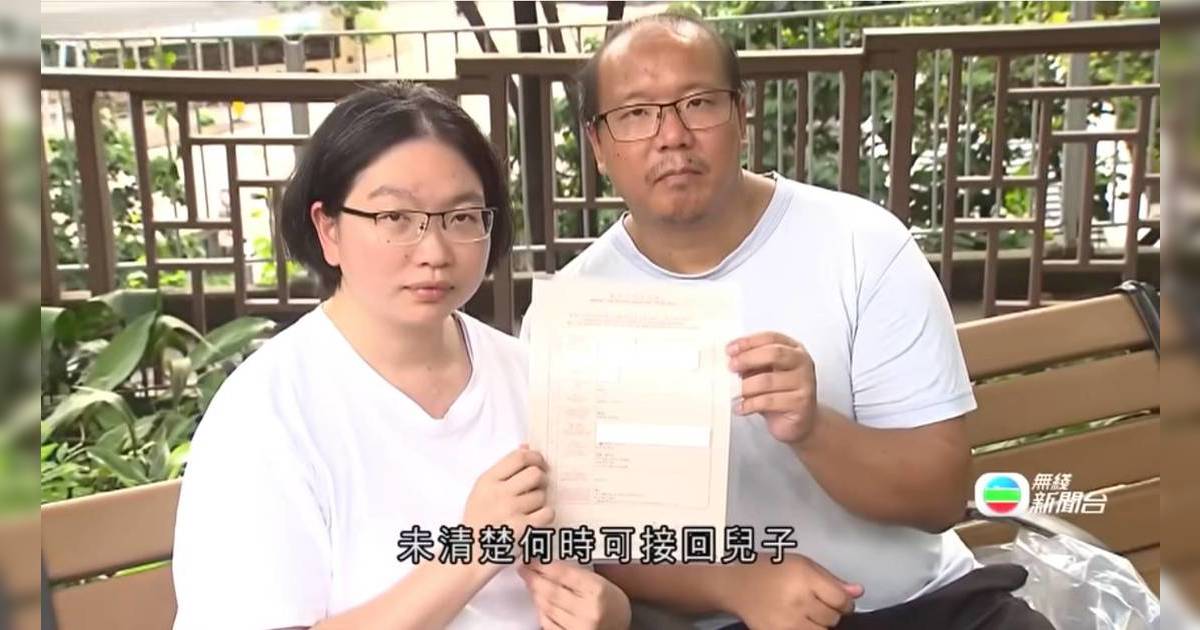

始作俑者陳醫生一直以病假為由失聯,葉女士連索取自己的醫療報告亦困難重重。然而,網上關於陳醫生的負評卻是鋪天蓋地,不少網民留言指他是「可怕的牙醫」、「態度好差」、「脾氣暴躁」。更令人震驚的是,早在2019年已有另一位苦主發文,控訴被同一位陳醫生進行剝牙手術後,因殘留牙碎導致發炎。面對診所的冷處理,《東張西望》攝製隊曾嘗試上門尋訪,但職員卻立即召喚保安將他們驅離。